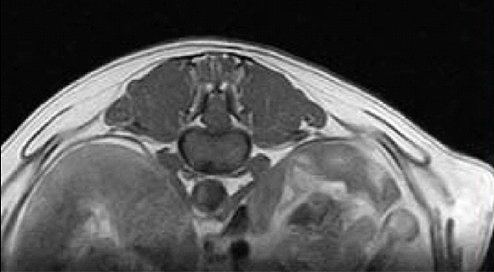

【画像診断】~ダックスフンド、雄10歳、グレート3の椎間板ヘルニア~

▲椎間板ヘルニアがあるMRI像T13-L1の頭側像、造影後のT1強調画像(キャミックに依頼)

▲椎間板ヘルニアがあるMRI像、T13-L1の尾側像、造影後のT1強調画像(キャミックに依頼)

▲椎間板ヘルニアがあるMRI像、T13-L1の造影なしのT2強調画像(キャミックに依頼)